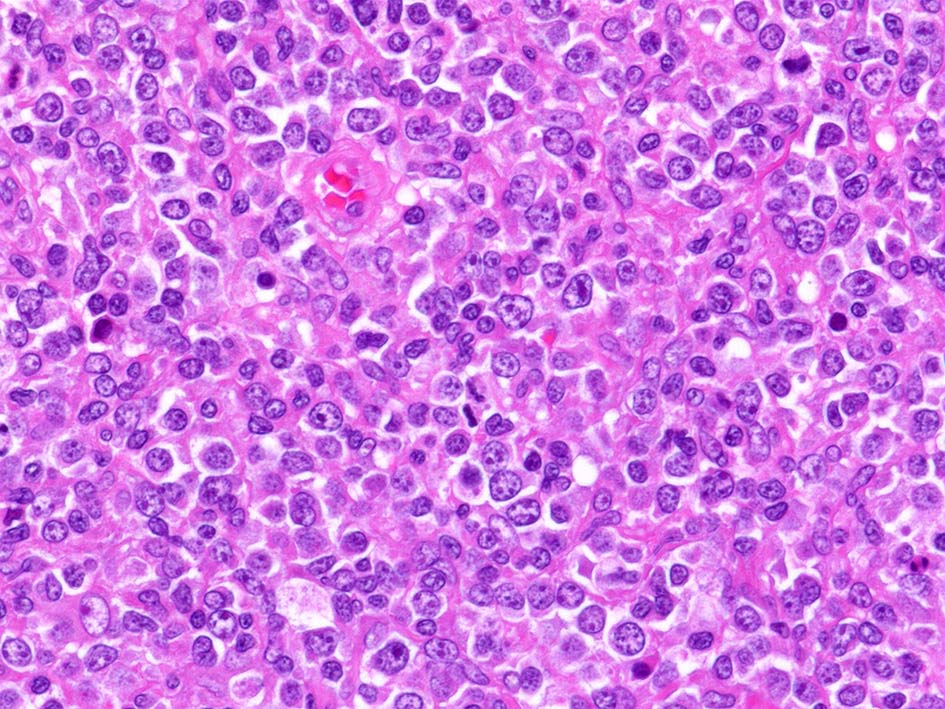

精細管は浸潤により萎縮, 消失. びまん性にcentroblasts/immunoblastsの増殖が認められる. 腫瘍細胞間に軽度の線維化がある.

小リンパ球と同程度か1.5倍くらいのサイズ, round/ convoluted nucleiをもつリンパ球がシート状密に増殖する. 核クロマチンは粗で, 核小体が認められる核もある.

DLBCLとは細胞の大きさや細胞所見が異なっている. 精細管への浸潤, 占拠所見がある.